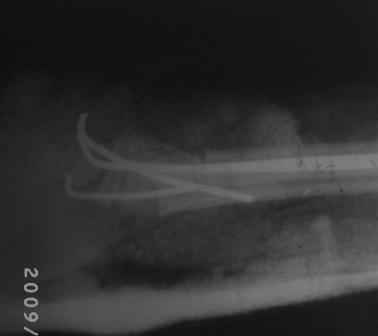

19.08.09г, на форуме был представлен случай: мальчик.13 лет, с артрогрипозом. Позже Евгений Чекашкин просил представить результаты лечения, поэтому , как раз больной на днях пришел для снятия гипсовой повязки, и решил показать что случилось. Оперировал 1,5 месяц назад, транспозиция сухожилий лучевой и локтевой сгибателей на тыл,тенотомия ладонного сухожилия, укорачиваюшая остеотомия костей п/плечья в дистальной трети,фиксация спицами в положении экстензии 15гр. После снятия гипса разгибание пальцев хорошие, сгибание ограничены, назначены ФТЛ, массаж и ЛФК, Больной и родители довольны результатом, я сам не очень! Фото и Р-снимки прилагается. Хочу выразить благодарность Ольге Агранович, А. Челнокову, Е. Чекашкину,Устьянцев Ибрагимову, ПОЗДРАВИТЬ ВСЕХ С НАСТУПАЮШИМ НОВЫМ ГОДОМ! С уважением Абдурашид.

Поздравляю с результатом , хочу надеяться, что ЛФК и Физио улучшит силу сгибателей пальцев и ребенок обрететнормальную функцию кисти. ВСё понятно с укорачивающими остеотомиями и сухожильными транспозициями, не понятно, почему Вы решили выполнить фиксацию дист л.к. спицами в положении 15 гр. экстензии- приводит к подвывиху в дист радио-ульнарном сочленении (страдает пронация -супинация) и ограничение сгибания кисти, уменьшается сила кистевого захвата - почему бы не ограничиться только укорачивающей

остеотомией и сухожильной транспозцией?

\\--H.L. Friedlander с соавт. (1968), U.Mennen (2003) при лечении сгибательных контрактур лучезапястных суставов выполняют укорачивающую остеотомию лучевой и локтевой костей в дистальной трети [11, 14]P.R. Weeks (1965) указанные вмешательства дополняет отсечением длинной ладонной мышцы, иссечением части фасции предплечья, ладонной капсулотомии лучезапястного и межзапястных суставов. Фиксация кисти осуществляется спицами Киршнера в полоржении тыльной экстензии под углом 15°. Укорочение костей предплечья предотвращает возможность возникновения ишемии локтевого и срединного нервов после коррекции деформации [18]-\\.

Во время операции, после укорочении костей предплечья и репозиции , кисть оказался в положение сгибания где-то под углом 15гр., поэтому фиксация произведена под 15гр. экстензии.

Волярный наклон суставной фасетки лучевой кости в норме составляет 9 градусов, а у вашего пациента фасетка наклонена на 40 градусов в тылную сторону, это значит что угол смещения равен 49 градусам.

Нужно повторить снимки лучезапястного сустава в 2х проекциях, т.к. предоставленные снимки не качественные, они нужны для изучения радиоульнарного угла и дистального радиоульнарного сустава, это очень важно.

Вы совершенно правильно процитировали фрагмент статьи О.Е.Агранович. Но не обратили внимание, что укорочение предплечья проводится исключительно с целью профилактики неврологических осложнений!!!! Причем перечисленные вами авторы корригируют деформацию на уровне лучезапястного сустава (капсулотомия по ладонной поверхности, отсечение и перемещение сухожилий) или путем интеркарпальной резекции (О.Е.Агранович). Но ни один из авторов не корригирует деформацию на уровне костей предплечья после укорочения последних, так, как сделали вы.

Вы, тем самым, получили двойную деформацию-еа уровне дистальных метафизов костей предплечья и зоне лучезапястного сустава. Самое главное-небольшой возраст пациента приведет к самоисправлению деформации костей предплечья и рецидиву контрактуры.